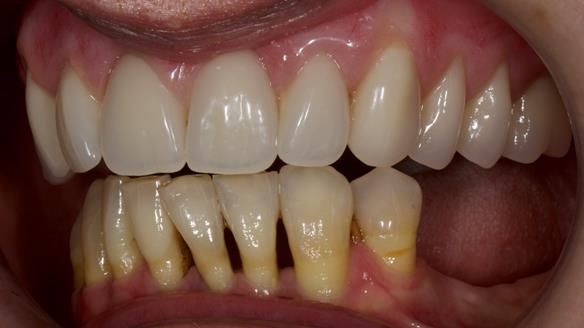

She had previously suffered from generalised periodontitis – stage IV, grade C, currently stable, with reduced attachment across the upper arch.

By the time she came to me, her periodontal condition was stable — but the aesthetics in the upper jaw were very poor.

Dr Syed Abad — my colleague and a Specialist in Periodontics — had successfully stabilised her gum health.

We provided her with an immediate upper denture (Mk 1), followed by a definitive metal-based upper denture (Mk 2). A lower removable partial denture was discussed, to be made only if needed once the upper treatment was complete. However, at review, this wasn’t necessary — Adnana had excellent neuromuscular control and function, even with a shortened dental arch (SDA).